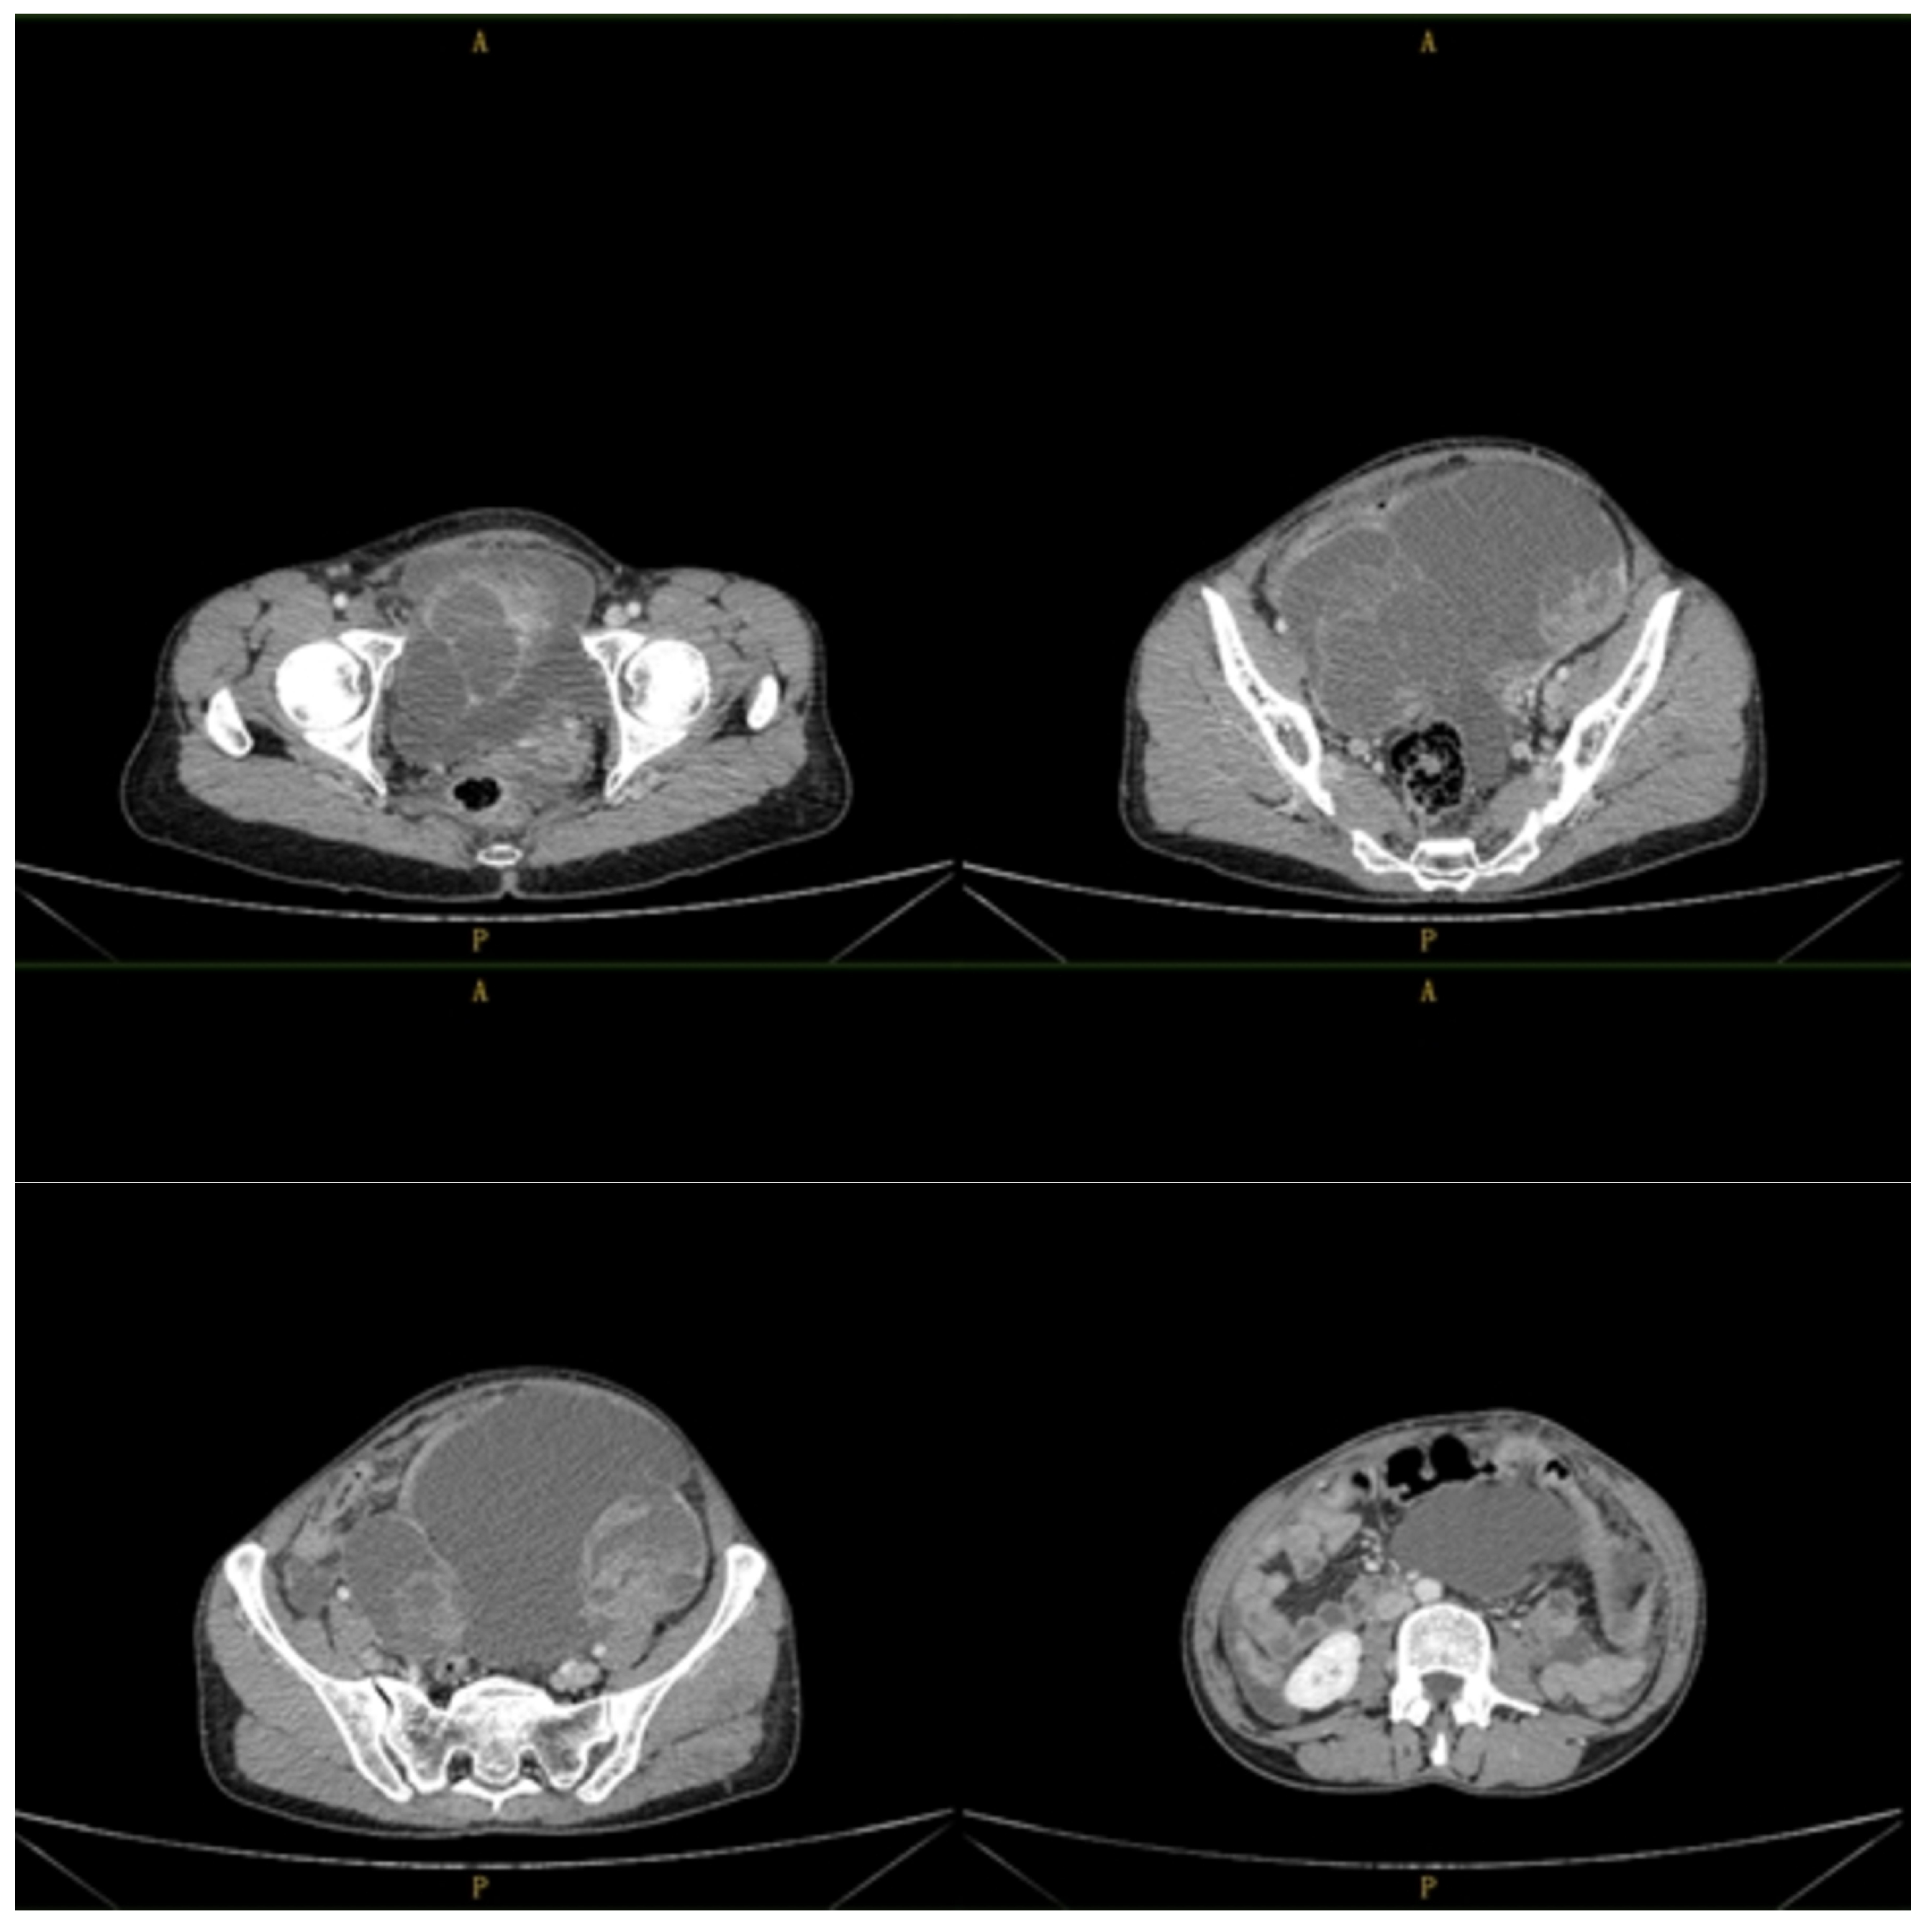

2. Detailed Case Description

2.1. Clinical Presentation